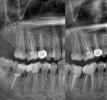

علاج الزرع السني